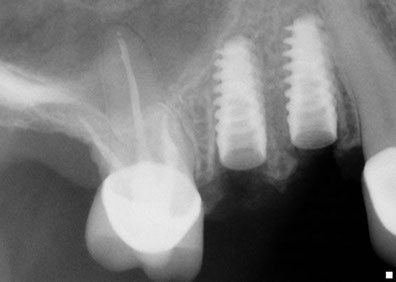

Una solución rápida y segura para hacer posible la instalación de implantes dentalesFue Philip Boyne, quien en 1960 utilizo por primera vez la técnica Caldwell-Luc, empleada para corregir la falta de espacio maxilo-mandibular elevando la Membrana Sinusal en la zona de molares y premolares, colocando en la base del seno un injerto compuesto por hueso particulado o corticoesponjoso autógeno (que se origina o engendra a sí mismo ) para el relleno de esta cavidad ósea, con la llegada de los implantes de titanio radiculares, se observó que muchas zonas maxilares posteriores, eran inadecuadas en altura y anchura ósea, por lo que se requirió injertar hueso dentro del seno maxilar para hacerlas adecuadas receptoras de implantes. La elevación de senos, es una técnica quirúrgica necesaria cuando no hay suficiente hueso, se añade hueso entre el maxilar superior y los senos maxilares, que son un anexo de las fosas nasales por lo que están en ambos lados de la nariz, la forma y el tamaño de este seno varían en cada persona y con el paso de los años se va haciendo más grande (inadecuado para implantes dentales).

Esta técnica es empleada en cirugía dento-alveolar, oncología y traumatología, con el objeto de dar arreglo a un defecto óseo craneofacial etc. La elevación de seno es una solución segura a través de la cual es posible la instalación de los implantes dentales osteointegrados, dando como resultado estética y funcionalidad a la dentadura, este procedimiento es también conocido como Sinus Lift.

Hace ya más de 15 años que esta técnica se ha vuelto usual, En Dental Evolution Cancún hemos logrado una óptima calidad de injerto óseo con lo que el periodo de formación ósea se ha reducido considerablemente, la cirugía se realiza bajo anestesia local o sedación y su duración es menor a dos horas.

¿Para quién esta indicada esta técnica?Esta técnica esta recomendada en aquellos casos donde es imposible colocar implantes dentales con la longitud óptima en la parte posterior del maxilar superior ya que en esta región se posee generalmente una calidad ósea Tipo III ó IV y por esto es necesario utilizar implantes de una longitud mínima de 10mm y del mayor diámetro posible.